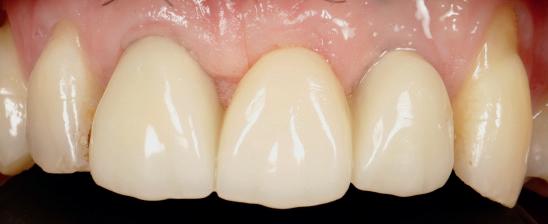

Adults could one day grow their own replacement teeth instead of having fillings – as scientists make a key discovery. This research offers a potential way to repair teeth and a natural dental treatment alternative.

Unlike implants and fillings, which are fixed and cannot adapt over time, a labgrown tooth made from a patient’s own cells could integrate seamlessly into the jaw and repair itself like a natural tooth.

In the latest study, the King’s team, in collaboration with Imperial College London, made a key discovery on the environment needed to grow teeth in the lab. They have now successfully introduced a special type of material that enables cells to communicate between each other. This means that one cell can effectively ‘tell’ another to start differentiating into a tooth cell. This mimics the environment of growing teeth and allows scientists to recreate the process of tooth development in the lab.

Xuechen said: “We developed this material in collaboration with Imperial College to replicate the environment around the cells in the body, known as the matrix. This meant that when we introduced the cultured cells, they were able to send signals to each other to start the tooth formation process.

“Previous attempts had failed, as all the signals were sent in one go. This new material releases signals slowly over time, replicating what happens in the body.”